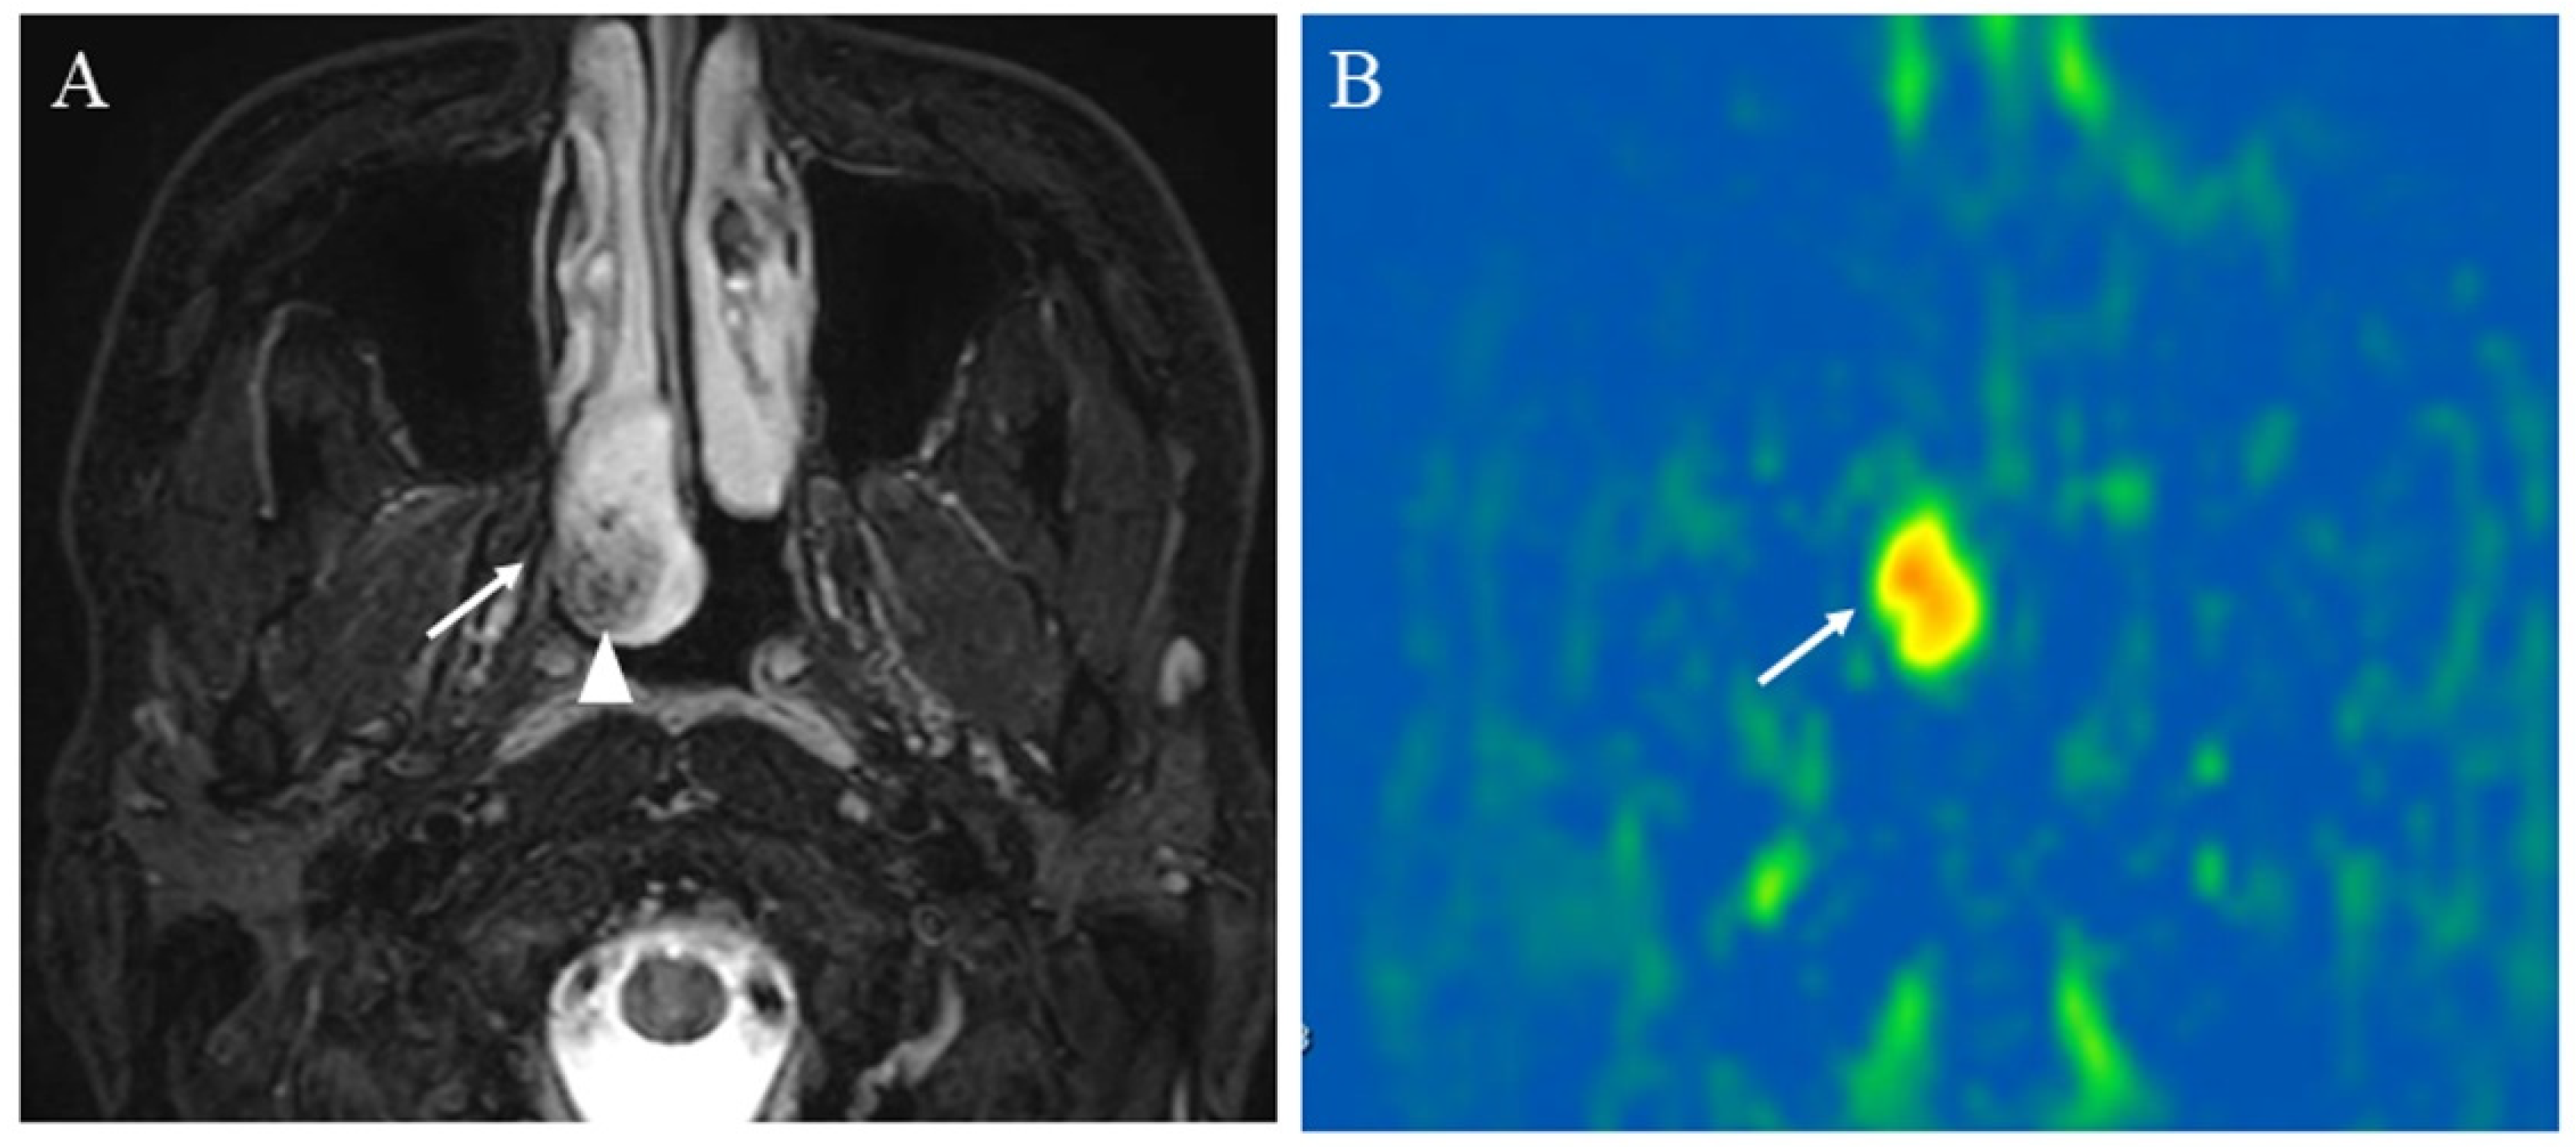

Figure 6. An 83-year-old female with the right carotid body paraganglioma: (A) T2-weighted image shows a right cervical mass (arrow) at the carotid artery bifurcation with high signal intensity and flow voids or salt and pepper appearance within the mass (arrowhead); (B) pCASL image shows abundant blood flow within the lesion (arrow) (mean of 303.04 mL/100 g/min).